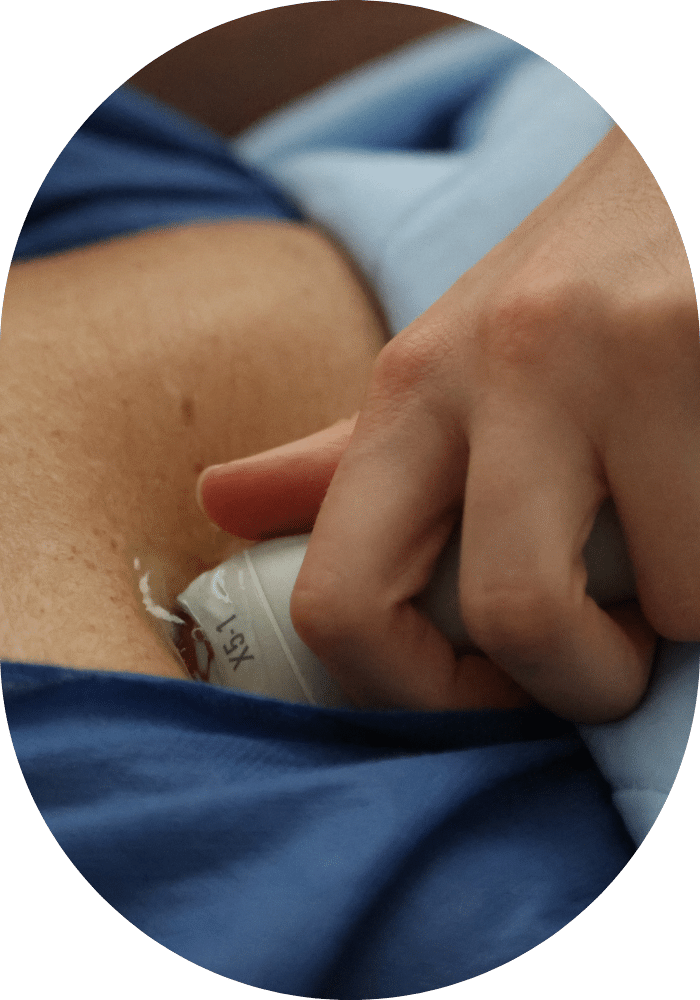

Echocardiographie transthoracique

L’échocardiographie transthoracique est un examen utilisé pour générer des images du cœur (cavités cardiaques et valves) et des gros vaisseaux (aorte, artère pulmonaire et veines caves). Des séquences sont réalisées sur plusieurs axes ou coupes et analysées en temps réel par le cardiologue ou le technicien spécialisé qui effectue l’examen. C’est exactement le même principe qu’une échographie dans le cadre d’un suivi de grossesse, mais au niveau du thorax.

Cet examen peut être utile en cas de suspicion d’une maladie cardiaque (par exemple si l’on présente des douleurs thoraciques à l’effort, un souffle au cœur, des palpitations). Il sert également à évaluer l’efficacité d’un traitement ou pour suivre l’évolution d’une maladie. L’échocardiographie transthoracique est indolore, non invasive et dure en général de 15 à 30 minutes.